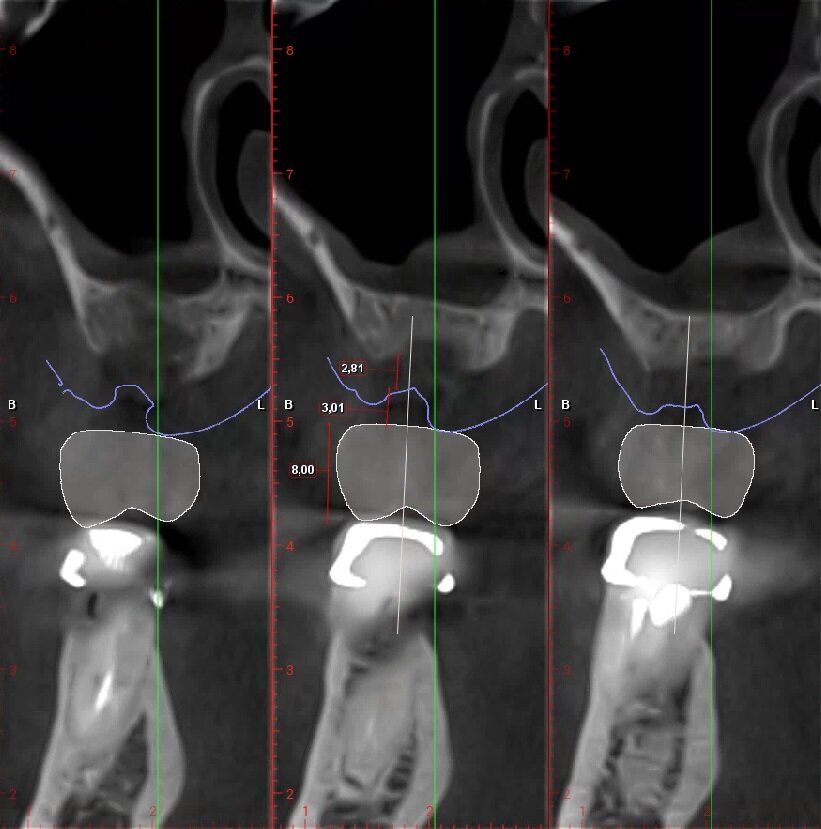

Fig. 4_Ceratura diagnostica elemento 2.5. Dimensione corono-apicale della corona congruente con elemento controlaterale 8,24 mm, tragitto trans-mucoso 3,03 mm, entità della rigenerazione ossea verticale necessaria 2,01 mm.

Fig. 5_Ceratura diagnostica elemento 2.6. Dimensione Corono-apicale della corona congruente con elemento controlaterale 8,00 mm, tragitto trans-mucoso 3,01 mm, entità della rigenerazione ossea verticale necessaria 2,81 mm.